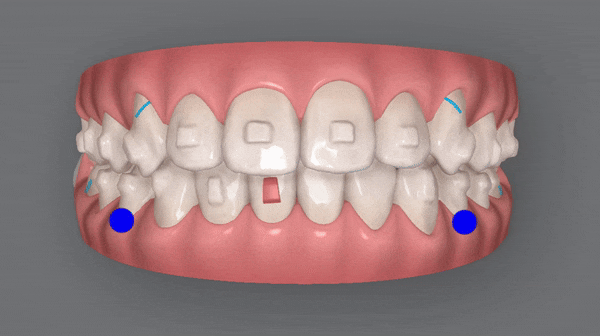

인비절라인 치료기간 22.01 ~ 24.06

세번째 클린체크를 마친 후 사진입니다

wow~!

치아 배열부터 교합까지

거의 완벽하게 마무리가 된것처럼 보이지만

꼼꼼한 닥터킴의 열정은 끝나지 않았는데요 ><

마지막 클린체크를 통해

마무리된 치아배열을 확인해 보실까요?

교정기간: 22/1~24/6

치열이 고르지 않고

송곳니가 도드라져 보였던 이전과는 달리,

청소년기인비절라인 교정 후

정중선이 맞아지고 치열이 가지런해지면서

보다 자연스러운 미소를 지어주었습니다.